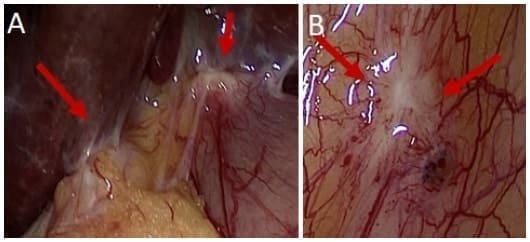

Ante la presencia de estadios T1b o más, se deben realizar estudios imagenológicos de estadificación clínica, que deben incluir imágenes de alta resolución de tórax, abdomen y pelvis, en busca de linfadenopatías regionales o metástasis a distancia (Figuras 2, 3 y 4), además se debe considerar la realización de una laparoscopia (Figura 5) 30.

Figura 5. Hallazgos laparoscópicos de compromiso peritoneal por cáncer de vesícula, dos meses después de colecistectomía vía laparoscópica por colelitiasis, con hallazgo inicial de CIVB. Siembras en el lecho quirúrgico (A) y siembra en el peritoneo parietal (B).